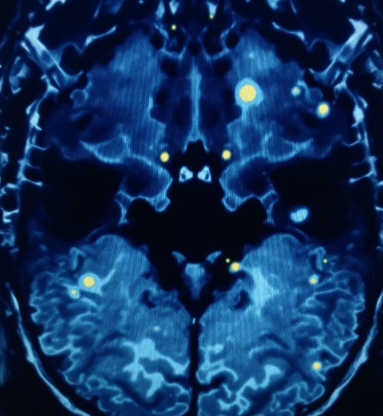

경도인지장애는 조기 발견과 관리가 가능한 인지 저하의 중간 단계입니다. 치매로의 진행 여부는 개인에 따라 다르며, 지금부터 어떤 관리를 하느냐가 향후 삶의 질을 결정짓습니다. 이번 글에서는 경도인지장애의 정의, 증상, 대처법을 총정리해드립니다.

경도인지장애(MCI)는 말 그대로 인지기능이 떨어졌지만 아직 일상생활에는 큰 지장이 없는 ‘중간 단계’ 상태입니다.